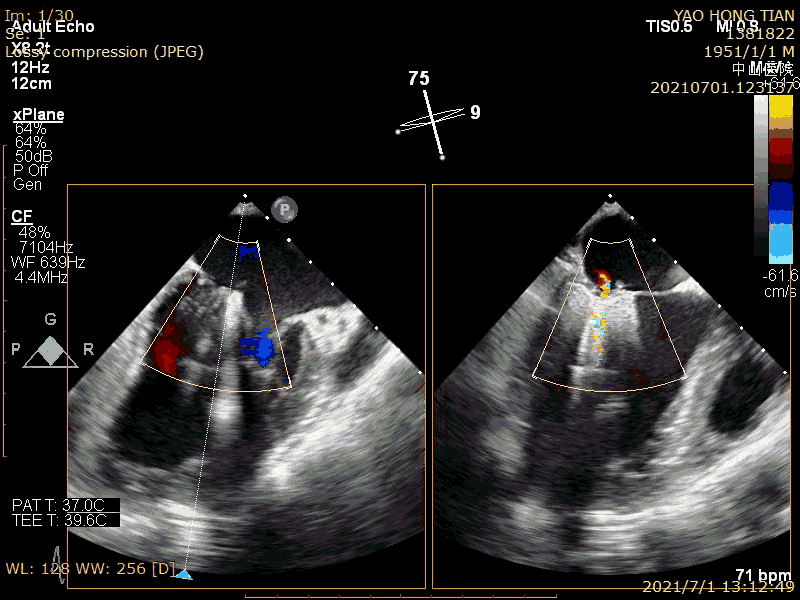

Effect evaluation after half-clipping

Effect evaluation after complete clipping